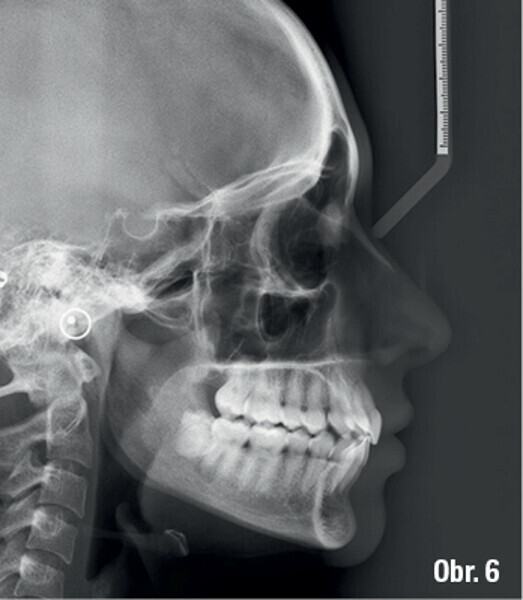

Distalizace horních molárů pomocí alignerů a cyklických sil